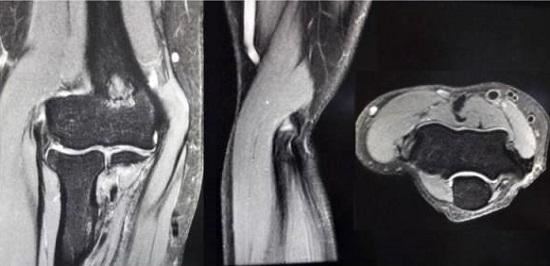

1、查体。用手指按压肱骨外上髁(上臂、末端外侧区域),会有比较明确的、敏锐的疼痛;在肘伸直、握拳、屈腕状态下前臂旋前,会在该区域出现显著疼痛;前臂旋前的情况下负重旋后,也会出现疼痛。中期和早期的患者,不会在肱骨外上髁处出现肿胀等异常表现,长期的患者可能会出现伸腕肌的萎缩。2、影像学检查。X光一般没有异常(比较严重者可能会有钙化点);超声波检查可能会发现肌腱纤维化、钙化等表现;MRI(核磁共振)检查可以较好地观察到软组织和骨骼病变,但对初期的病变仍难以探查。3、鉴别诊断。如有外伤史,或者是短期内出现的急性疼痛,亦或同时存在神经病变的症状(感觉缺失、烧灼痛等),应通过影像学检查、查体、病史询问等方式与骨折、韧带损伤、肌腱断裂、神经病变等疾病进行鉴别诊,。断。